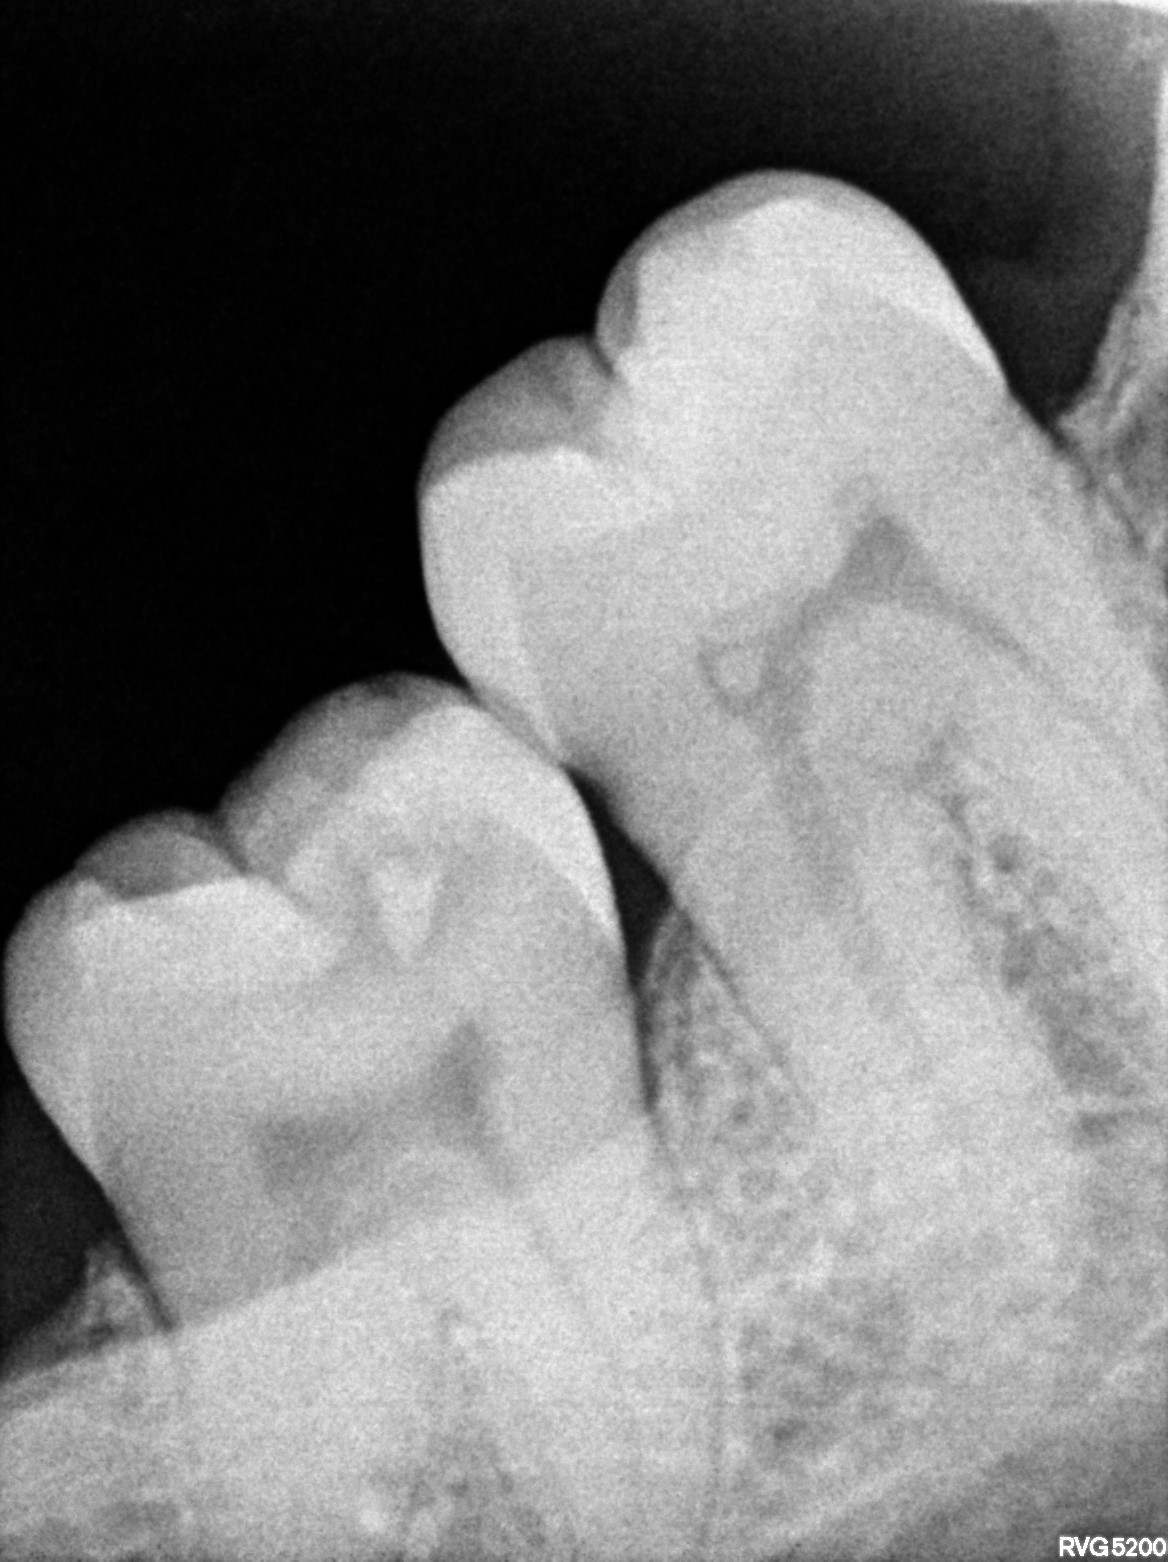

Dental Radiographs FHIR: DocumentReference · LOINC 24641-7

R56.jpg

24641-7